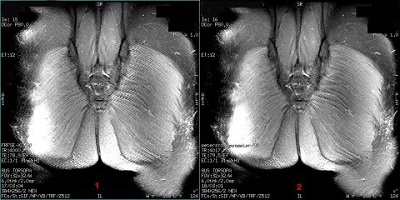

Enhanced Fine Line Suppression

Fine Line artifacts are often seen in odd NEX scans and result from unsuppressed FID signals. Use the Fine Line Suppression control variable to reduce this type of artifact with odd NEX FSE scans.

- Enter 0 to turn off (default state). It applies gradients in a particular manner for all 2D FSE prescriptions, is independent of the NEX selection, has a FOV and slice thickness cutoff (FOV </= 20 cm and slice thickness </= 6 mm), and 10% of the readout window is blanked out for true odd NEX scans.

- Enter 1 to turn on and increase certain gradient pulses for true odd NEX scans thus improving the reduction of fine line artifact on odd NEX scans. When turned on with odd NEX scans, it can result in a longer echo spacing (no more than 10%) and thus a reduction of slices per TR. This becomes apparent when switching between odd and even NEX since these trade-offs are not seen with even NEX scans. If the User CV Blurring Cancellation is turned on, the new version of enhanced Fine Line Suppression will always be used, independent of the choice of NEX. In other words, there will be no changes to the echo spacing or number of slices per TR with NEX.